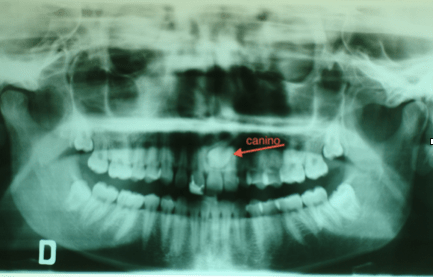

Non di rado accade che manchi in arcata il canino permanente superiore. Questo può essere dovuto a mancanza di spazio ma anche a problemi di eruzione del dente che si colloca lontano dalla propria sede. Nel caso di questa paziente, che presentava anche un grave morso coperto, il canino era dislocato palatalmente e molto distante dalla propria sede. Previo un piccolo intervento chirurgico è stato agganciato e portato in arcata.